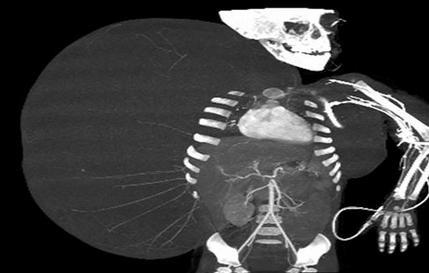

MEKSIKO SITI - Meksički doktori uspešno su uklonili 15 kilograma težak benigni tumor sa tela dvogodišnjeg deteta.

Lekari su rekli da je tumor bio teži od dečaka koji je u vreme operacije, 14. juna, imao 12 kilograma.

Dečak je rođen u državi Durango sa grbom koja je postepeno prekrila desnu stranu njegovog tela od pazuha do kuka.

Lekari La Raza medicinskog centra u Meksiko Sitiju su 10 sati uklanjali tumor. Ovo je inače prvi put da su meksički lekari uklonili tumor koji je veći od osobe koja ga je imala.